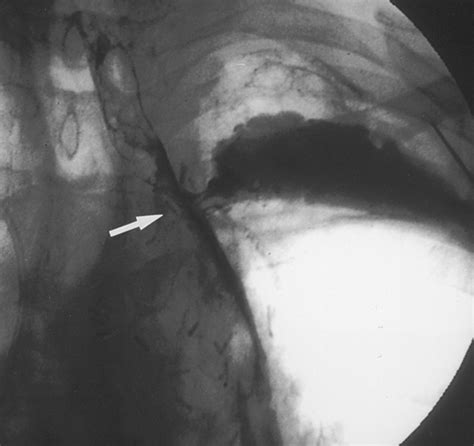

2. Measurement: Using X-ray imaging (fluoroscopy) or direct visual inspection, the physician measures the exact length and width of the obstruction to select the appropriately sized stent.

3. Deployment: The stent is loaded onto a delivery system and guided into the esophagus. Once positioned correctly across the blockage, the stent is deployed, where it expands against the esophageal walls.

4. Verification: The physician confirms the stent is properly seated before removing the delivery catheter.